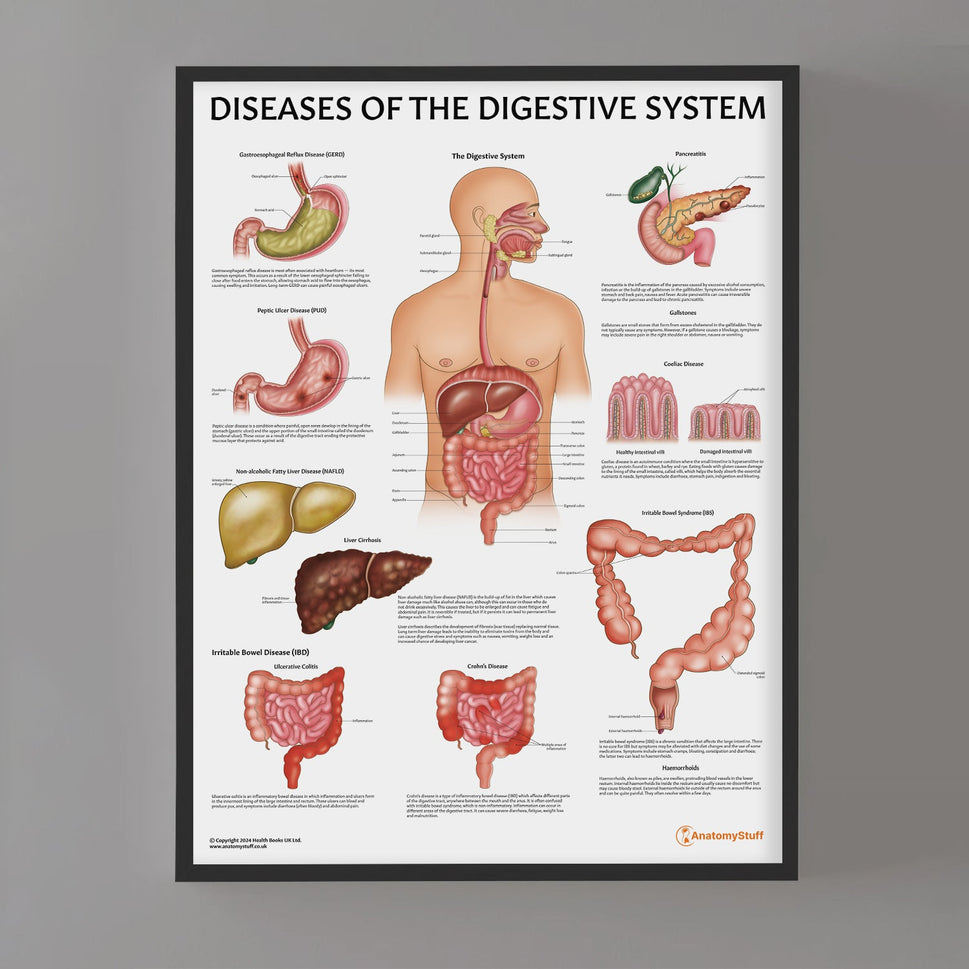

Enhance medical education with our collection of digestive system anatomical models including the stomach, liver, gallbladder, pancreas & colon models. Discover the anatomy of healthy organs as well as common gastrointestinal diseases such as stomach ulcers, gallstones and liver cirrhosis. Our digestive system anatomy posters are ideal for study and patient education.

At AnatomyStuff we stock a diverse range of digestive system anatomical models to suit your training needs. From budget models and affordable medical education posters to highly advanced 3D printed bowel models, you can transform medical training and patient education. As well as our own exclusive collection, we are proud resellers of 3B Scientific, Anatomy Lab, Denoyer-Geppert Science Company, ESP Models, Erler Zimmer and GPI Anatomicals. Explore our exclusive collection of digestive system anatomy charts, posters, fine art prints and digital anatomy study guides. Discover the anatomy of key organs like the liver, stomach, pancreas and bowel as well as the pathophysiology of common conditions like peptic ulcer disease, coeliac disease, IBD and much more. We have anatomy posters suitable for school children all the way up to medical degree level. From a liver anatomy poster to a digital study guide all about common GI disorders, find exactly what you need right here to enhance medical training and patient education.